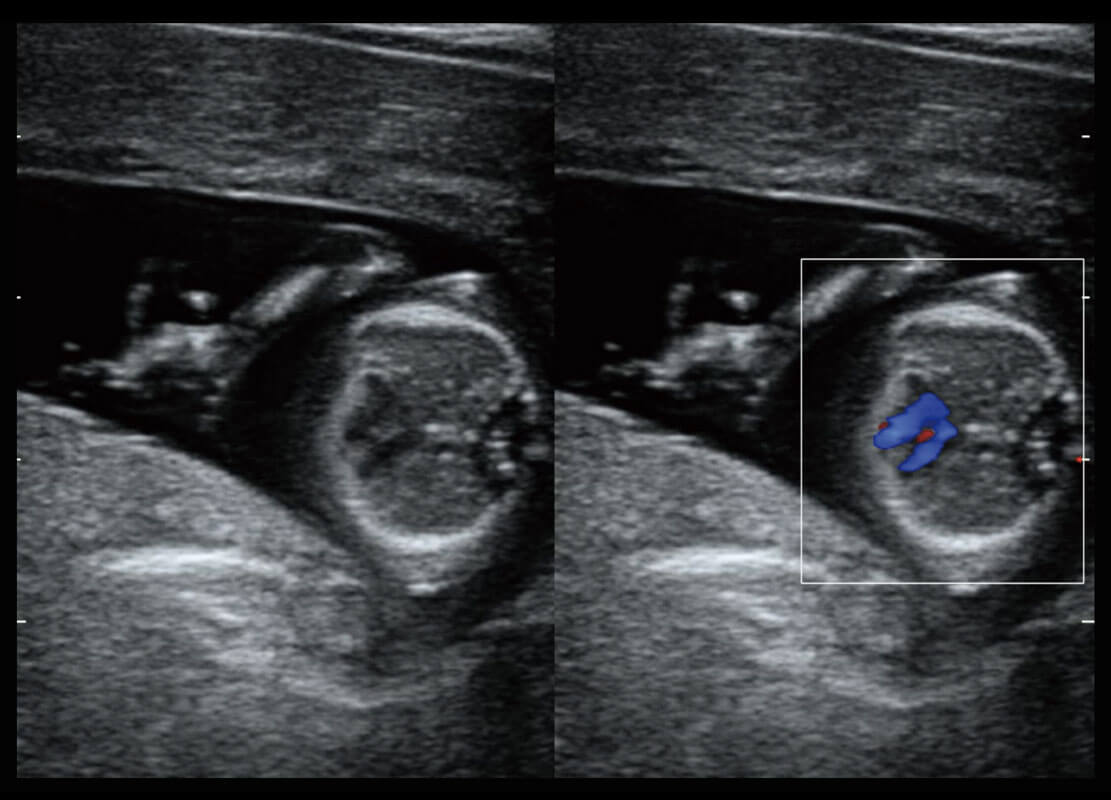

生殖健康

P60优异的图像质量搭载专科探头,在妇科基础疾病的诊断、卵泡生长的监测、输卵管通畅情况的判别等方面为您提供生殖应用方案。

• 腔内妇科-卵巢